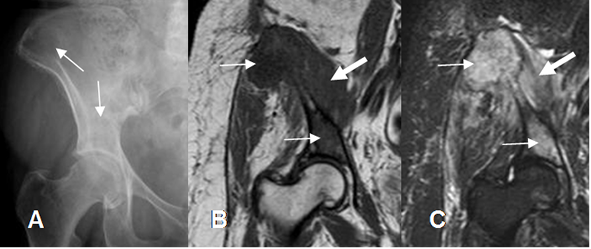

Fig 21. Edema óseo tumoral.

A: Rx AP. Lesiones líticas en el iliaco y por encima del acetábulo derecho.

B: RM coronal en T1 y C: RM coronal en STIR. Lesiones hipointensas en T1 e hiperintensas en STIR, por infiltración de la MO, secundario a metástasis de neoplasia de mama. (Flechas delgadas). Hay masa de tejidos blandos. (Flechas gruesas).